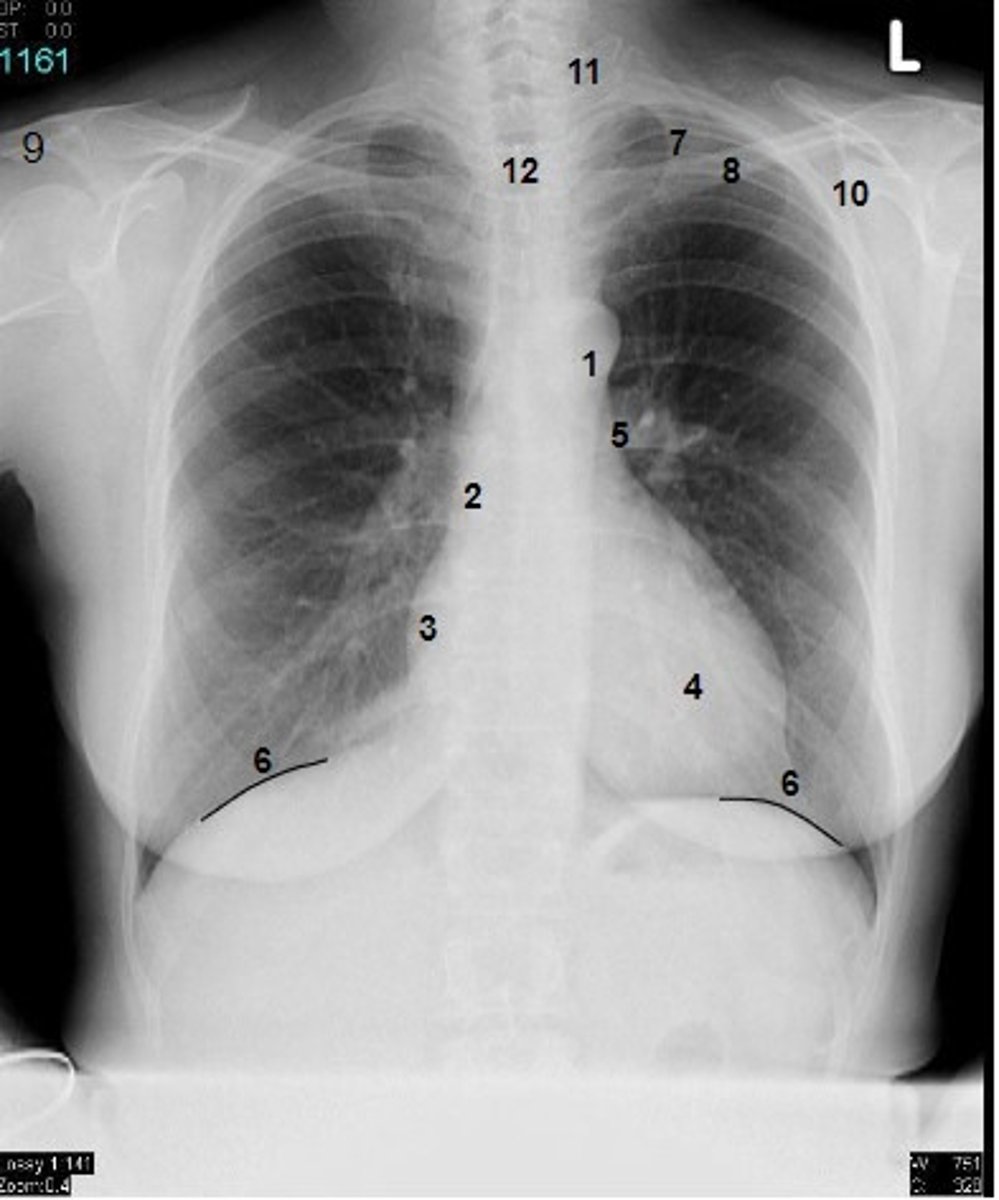

1

at what number is the arch of aorta?

2

at what number is the superior vena cava

3

at what number is the right atrium

4

at what number is the left ventricle

5

at what number is the primary bronchus

6

at what number is the dome of diaphragm

7

at what number is the first rib

8

at what number is the clavicle

9

at what number is the acromion of scapula

10

at what number is the coracoid process of scapula

11

at what number is the transverse process of vertebra

12

at what number is the spinous process of vertebra